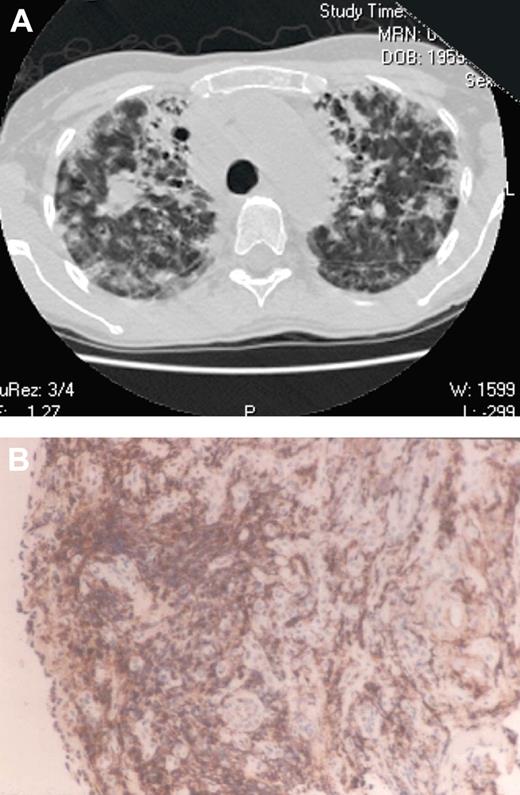

Lymphoid infiltrates in the lung leading to lymphoid interstitial pneumonia or follicular bronchitis/bronchiolitis without granuloma are equally challenging because they lead to cough, shortness of breath, alveolar damage, and ultimately, the need for oxygen therapy. Because of scarring and the predominance of T cells in the lung infiltrate (as shown in Figure 1), cyclosporine also has been used with benefit (125 mg a day; serum level 76 ng/mL).46 We have used cyclosporine in 2 subjects, with some stabilization of lung function for 4 years, but both patients succumbed to respiratory insufficiency, complicated by fatal acute hemolytic anemia in one of these subjects.31

Lymphocytic pulmonary infiltrates. (A) A 40-year-old woman with gradually worsening severe lung disease. Computed tomography of the chest revealed massive infiltrates composed of lymphocytic collections and fibrotic scars. (B) On biopsy, the infiltrating T cells in the lung, obliterating normal architecture, were revealed as CD4+ by the brownish monoclonal peroxidase conjugated monoclonal anti-CD4− staining pattern (magnification ×25).